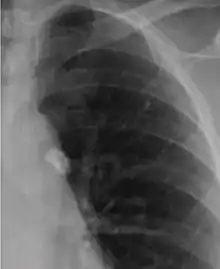

It is a small area of granulomatous inflammation, only detectable by chest X-ray if it calcifies or grows substantially (see tuberculosis radiology).[2] Typically these will heal, but in some cases, especially in immunosuppressed patients, it will progress to miliary tuberculosis (so named due to the granulomas resembling millet seeds on a chest X-ray).[2]

The classical location for primary infection is surrounding the lobar fissures, either in the upper part of the lower lobe or lower part of the upper lobe.[2]